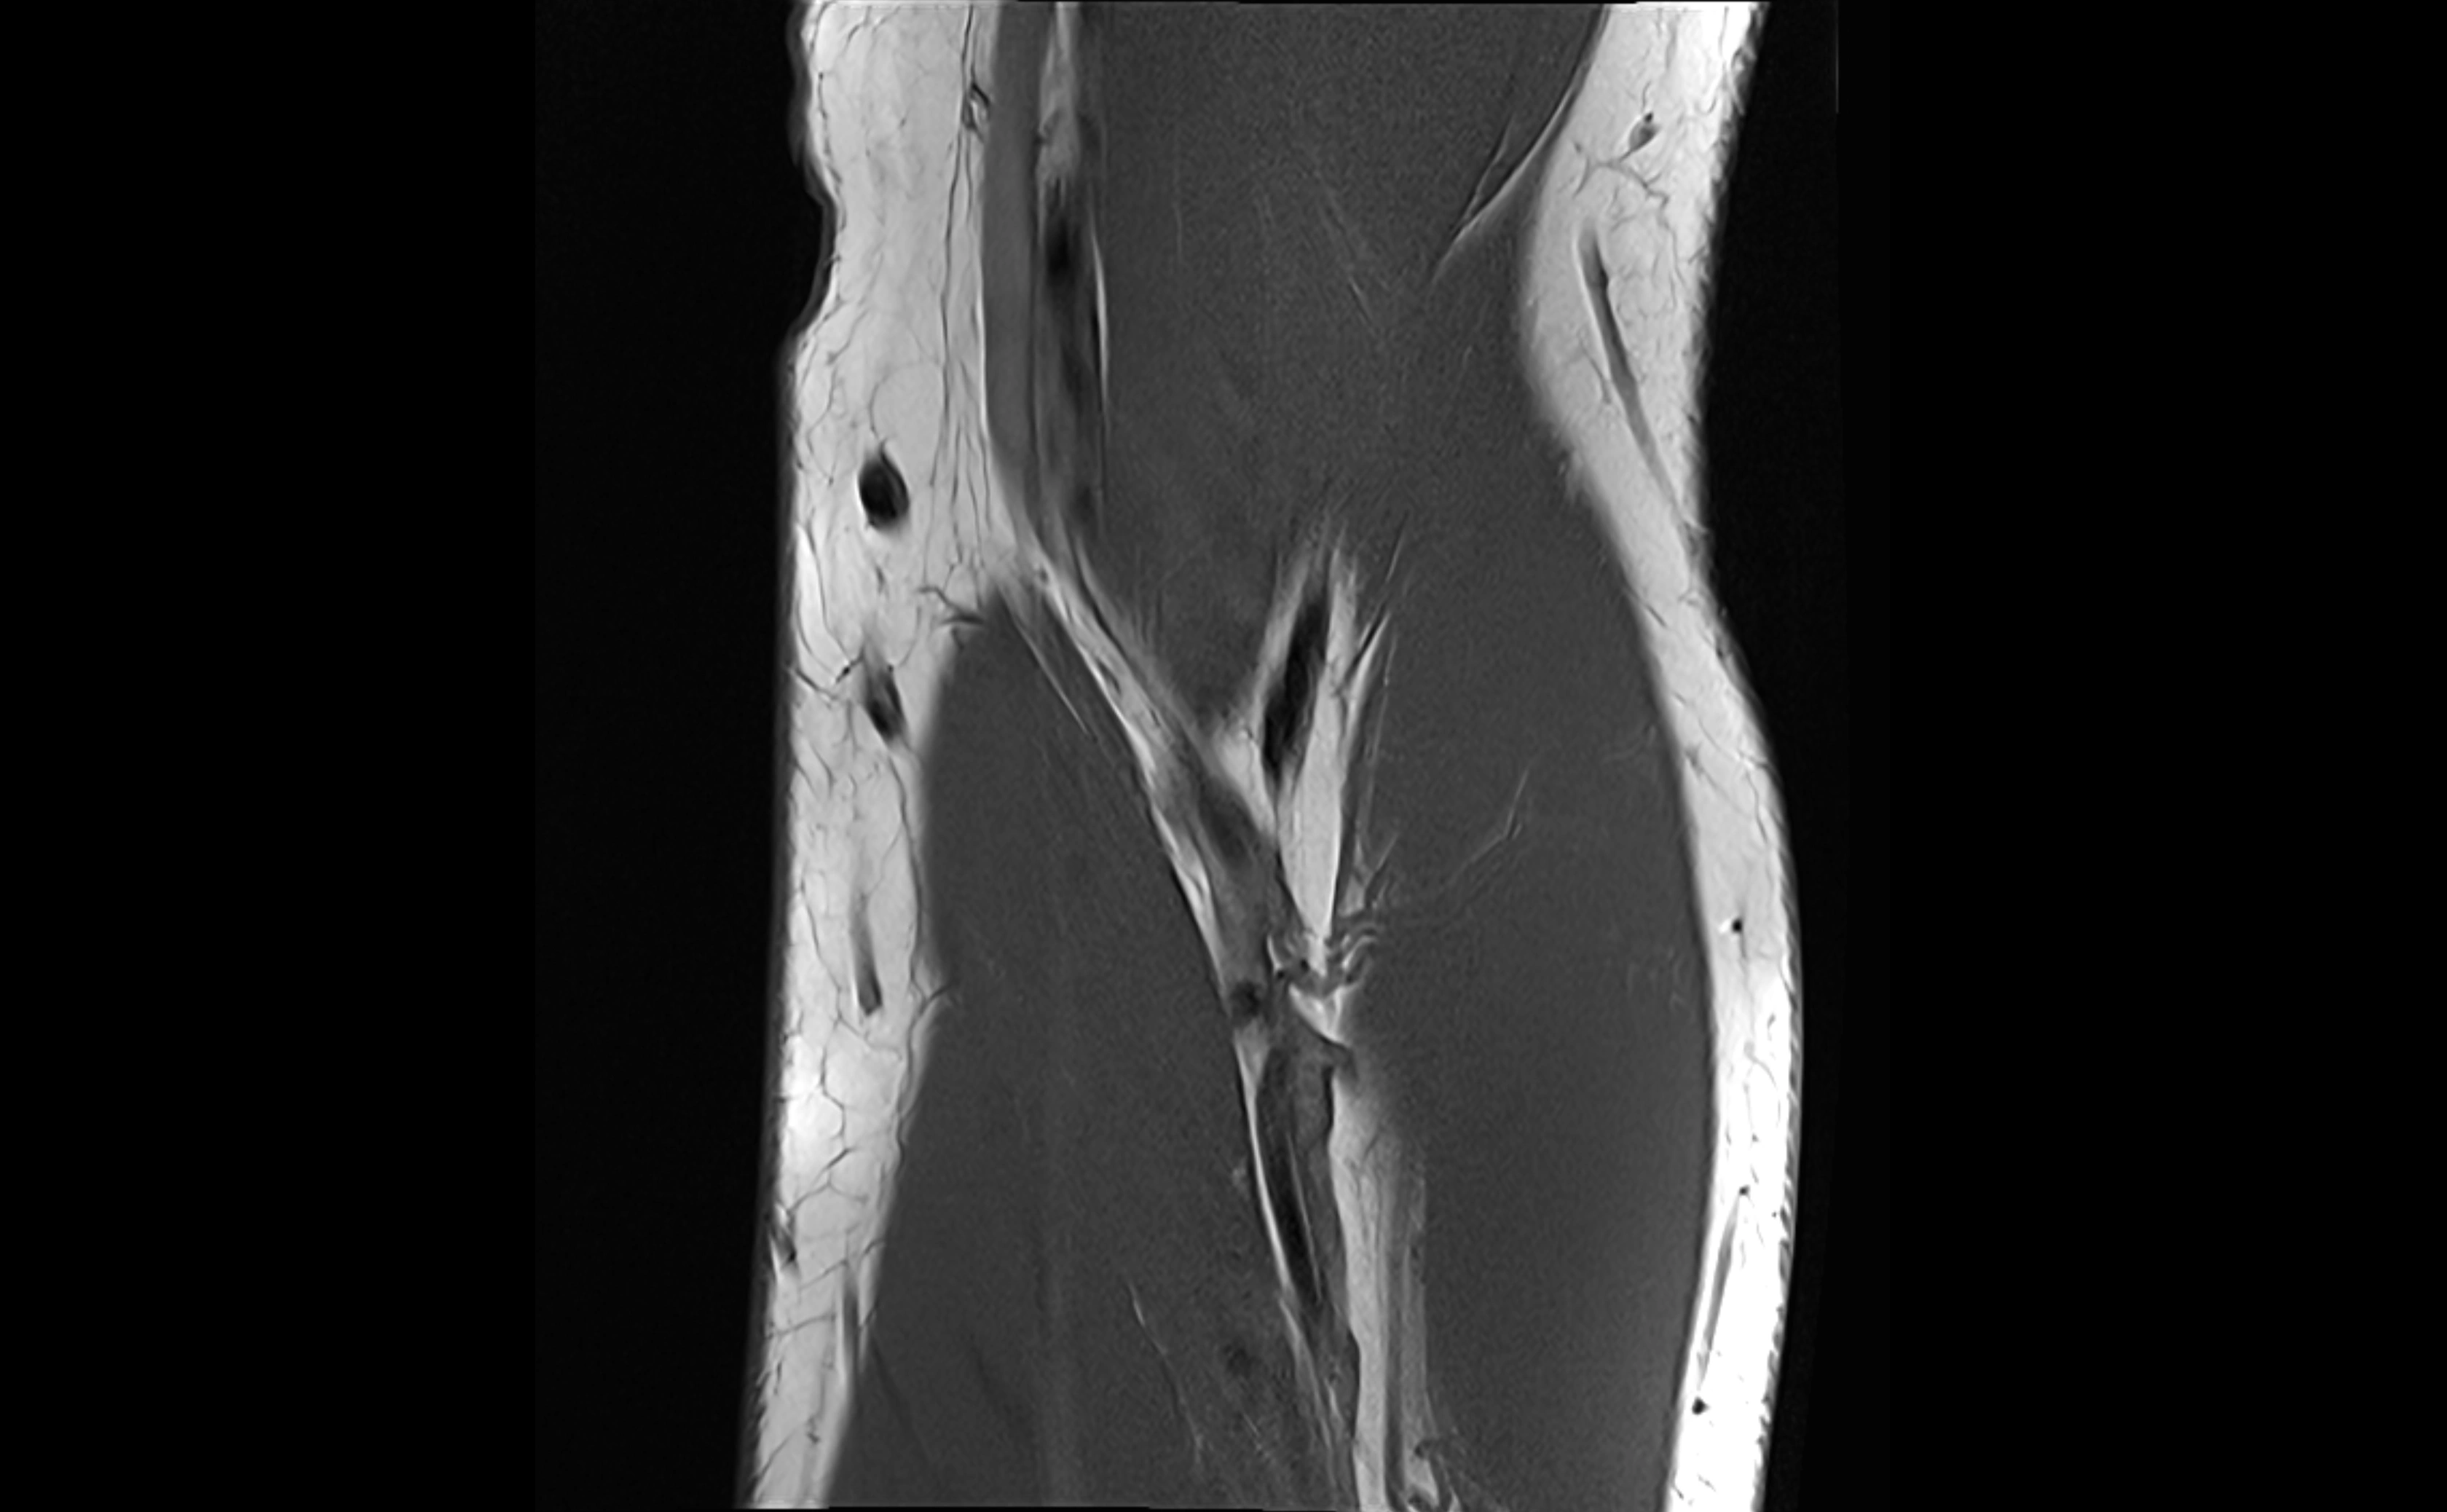

MRI images

image